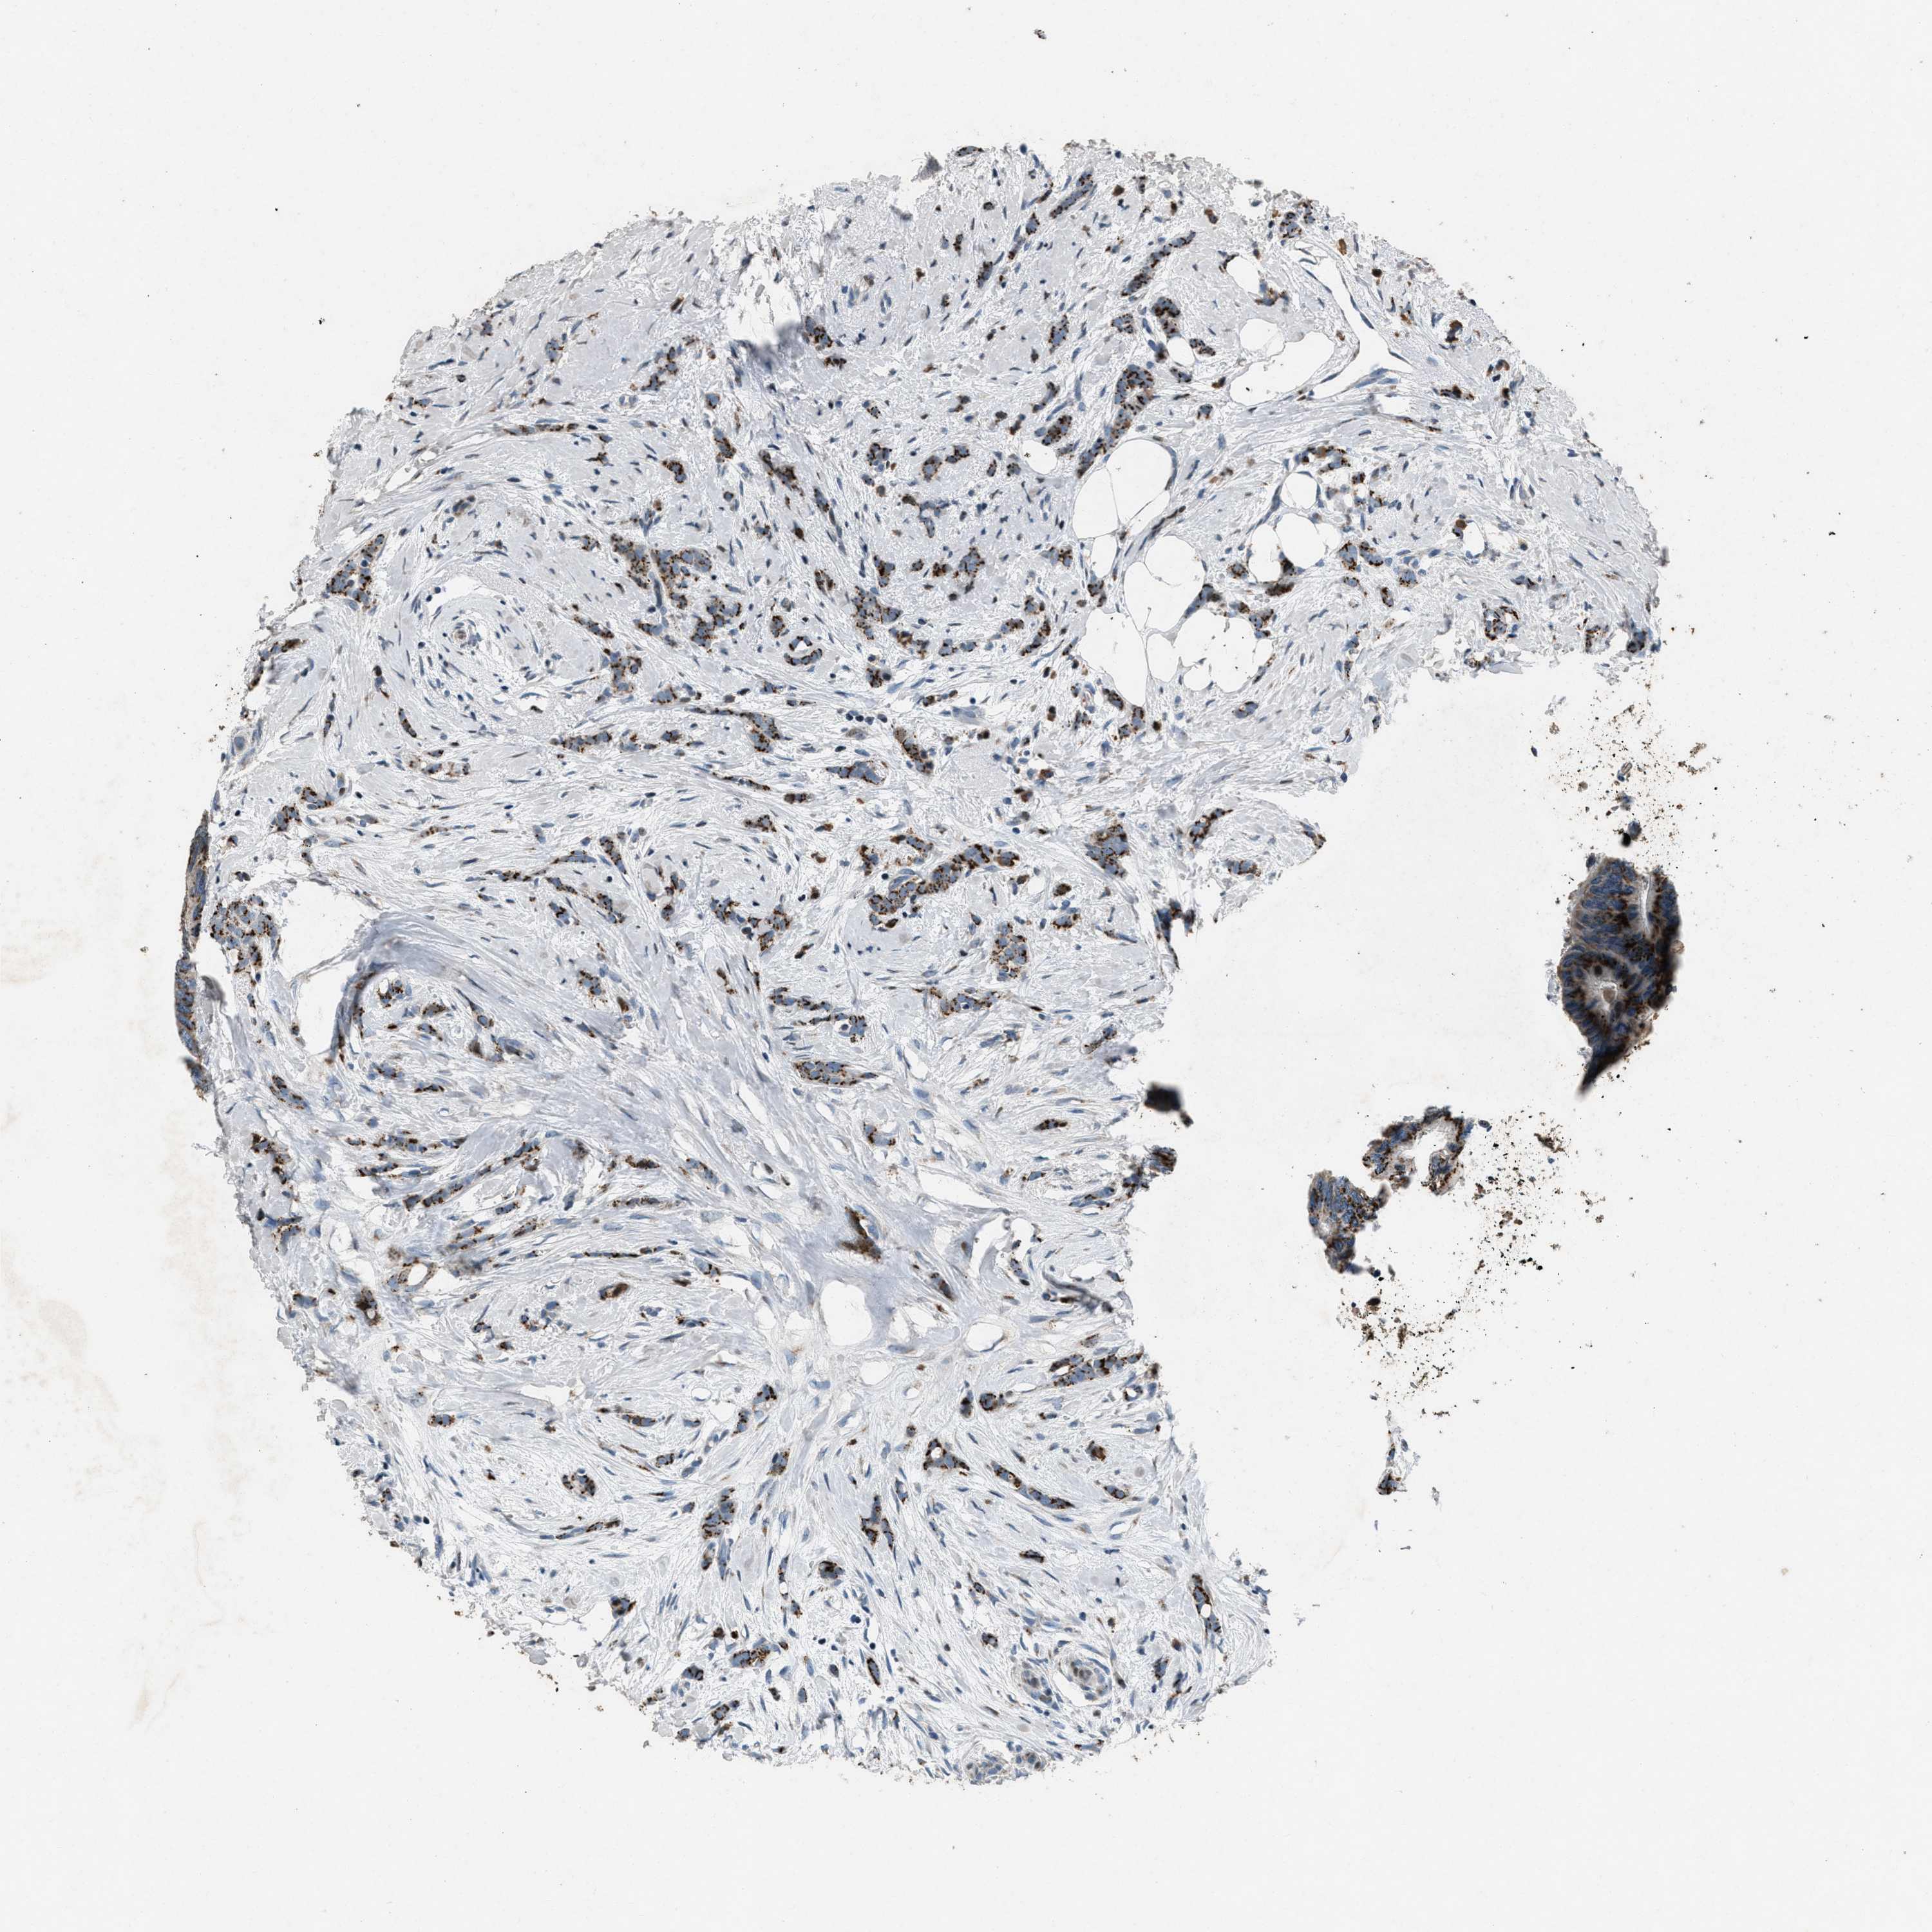

BRCA TCGA BRCA VALIDATION PROTEIN EXPRESSION

Breast cancer

Human cancer

Breast invasive carcinoma